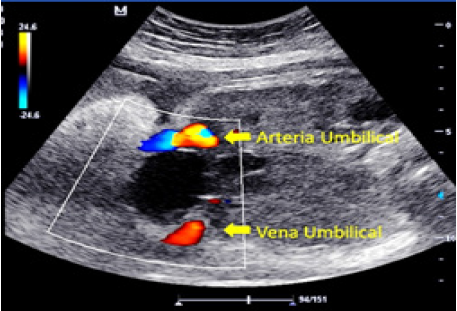

En el tercer trimestre de la gestación es referida a la Unidad de Perinatología de la maternidad de alto riesgo de la Ciudad Hospitalaria “Dr. Enrique Tejera”, donde se evalúa a las 32 semanas de gestación constatando los hallazgos antes descritos además de microftalmia (Figura 5), y arteria umbilical única (Figura 6), se solicita evaluacion prenatal por cardiología pediátrica y la ecocardiografía fetal concluye corazón estructuralmente sano.